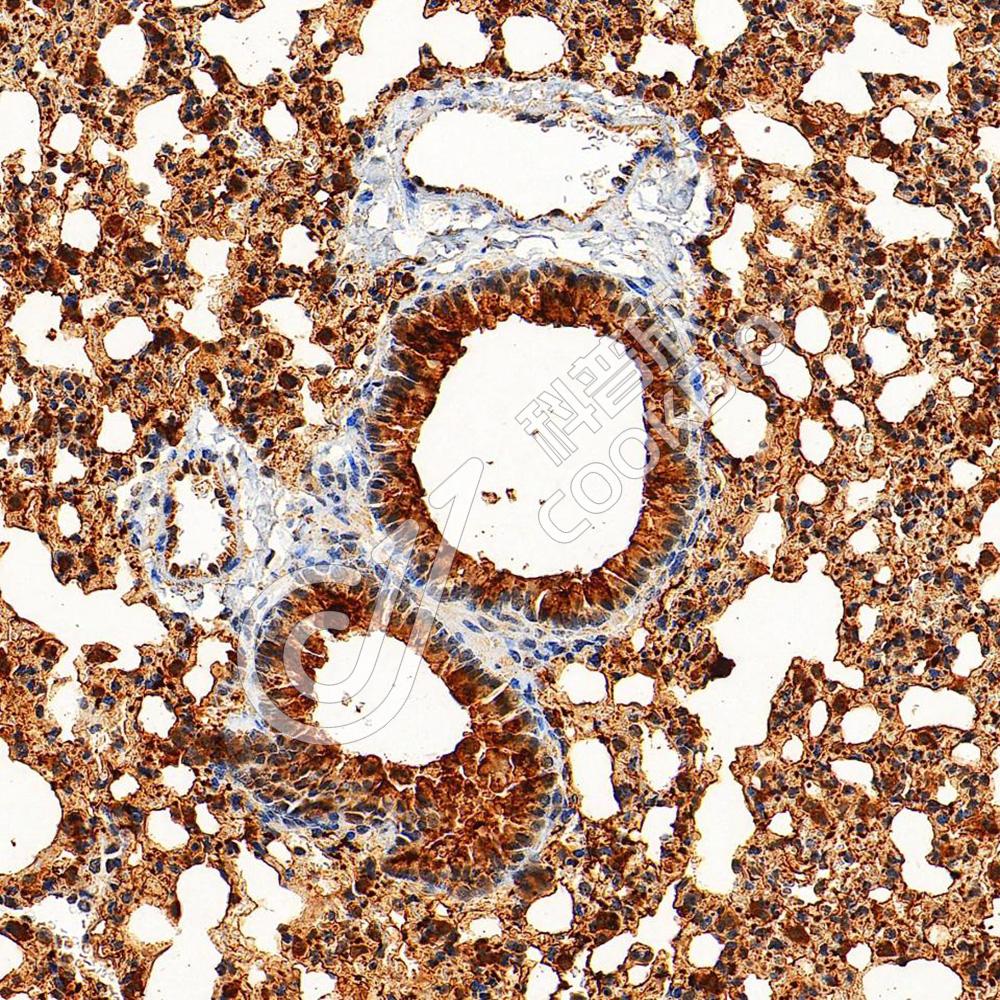

IHC检测SFTPA1蛋白(货号 K1342495).

样品: 大鼠肺, 4%多聚甲醛 (货号KSG1101) 固定12-24小时.

抗原修复: 柠檬酸抗原修复液(干粉, pH 6.0) (KSG1201), 98℃, 20分钟.

—抗: 1: 1500稀释, 4℃ 孵育过夜.

二抗: S-vision免疫组化多聚二抗(山羊抗兔),即用型 (货号KB3906), 室温孵育20分钟.